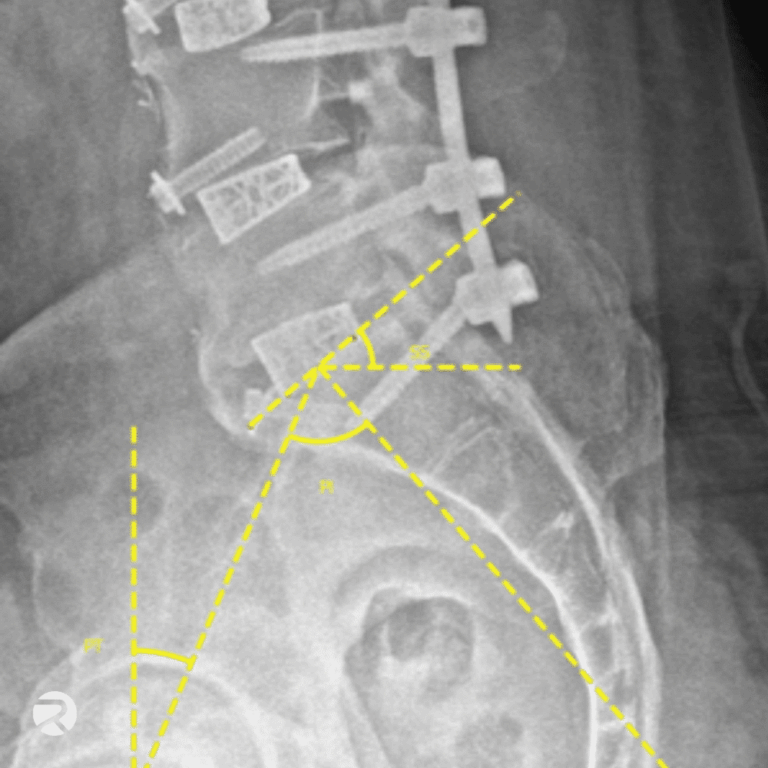

Accurate, Reliable, and Reproducible Spine Imaging Measurements

Conduct rapid and ultra-precise measurements for morphological parameters (Cobb Angle, Lordosis, etc.) and all major types of spinal therapies—including motion preservation, fusion, and deformity correction—and generate reliable, robust, and cost-effective spinal measurements for clinical research.

Spine measurements

- Range of Motion (RoM)

- Center of Rotation (CoR)

- Disc height

- Anteroposterior instability

- Cobb Angles

- Cervical & Lumbar Lordosis

- Segmental motion analysis

- Fusion assessment

- Implant subsidence

- And over 100 additional parameters

Spine

Selected morphoanatomical spine measurements and device performance metrics.

● Spinal Measurements

Angular Range of Motion (RoM, °)

Cobb Angles

● Device Performance Metrics

Implant Subsidence

Lordotic/Kyphotic Angle Restoration

- Löchel J, Putzier M, Dreischarf M, Grover P, Urinbayev K, Abbas F, Labbus K, Zahn R. Deep learning algorithm for fully automated measurement of sagittal balance in adult spinal deformity. Eur Spine J. 2024

Vertebral Height